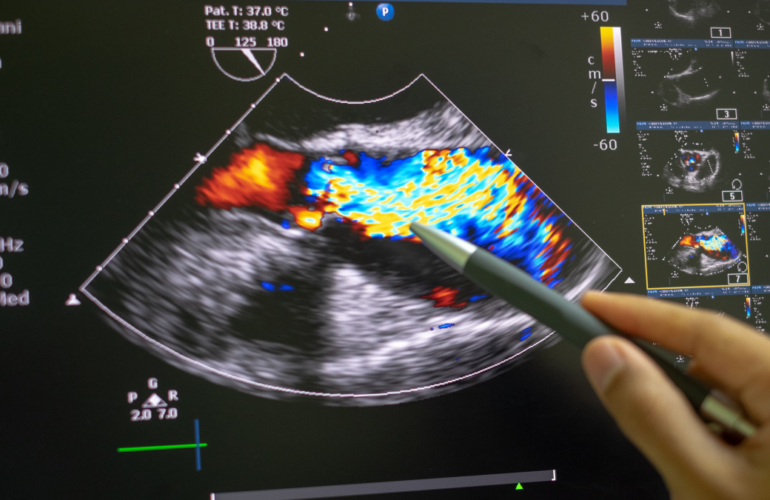

Echocardiography Essentials for Monitoring Heart Health

Echocardiography is a non-invasive ultrasound test used to evaluate heart health by producing images…